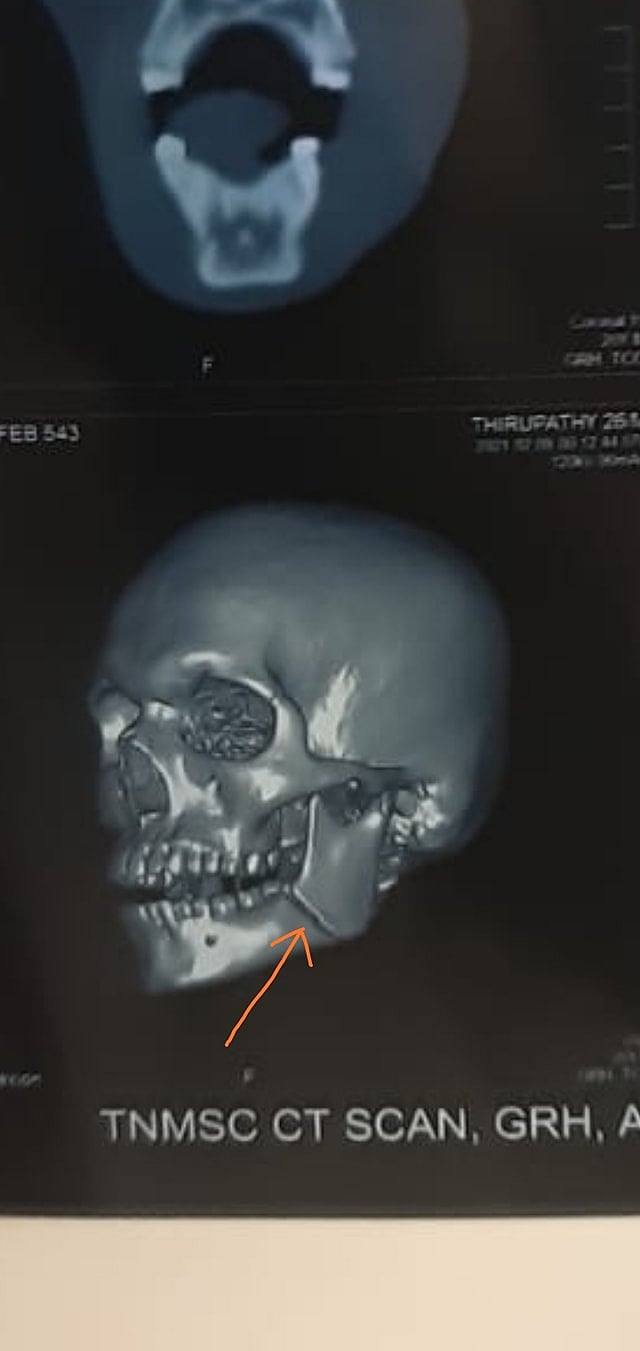

போலிஸார் 08.02.2021 தேதி இரவு அதாவது 09.02.2021 காலை 3.00 மணி அளவில் என்னிடம் வாக்குமூலம் வாங்கி சென்றவர்கள் மனு ரசீது எண். 90 /2021 Date; 09.02.2021 மட்டும் தந்தார்கள். சம்பந்தப்பட்ட போலிஸார் மீது எவ்விதமான வழக்கும் பதிவு செய்து மேல் நடவடிக்கை மேற்கொள்ளவில்லை. மருத்துவர்கள் எனக்கு எக்ஸ்ரே மற்றும் ஸ்கேன் எடுத்து பரிசோதித்து சிகிச்சை அளித்து வருகிறார்கள். மேலும் மருத்துவர்கள் எனது தாடையில் எலும்பு முறிவு ஏற்பட்டு இருப்பதாக தெரிவித்தார்கள்.